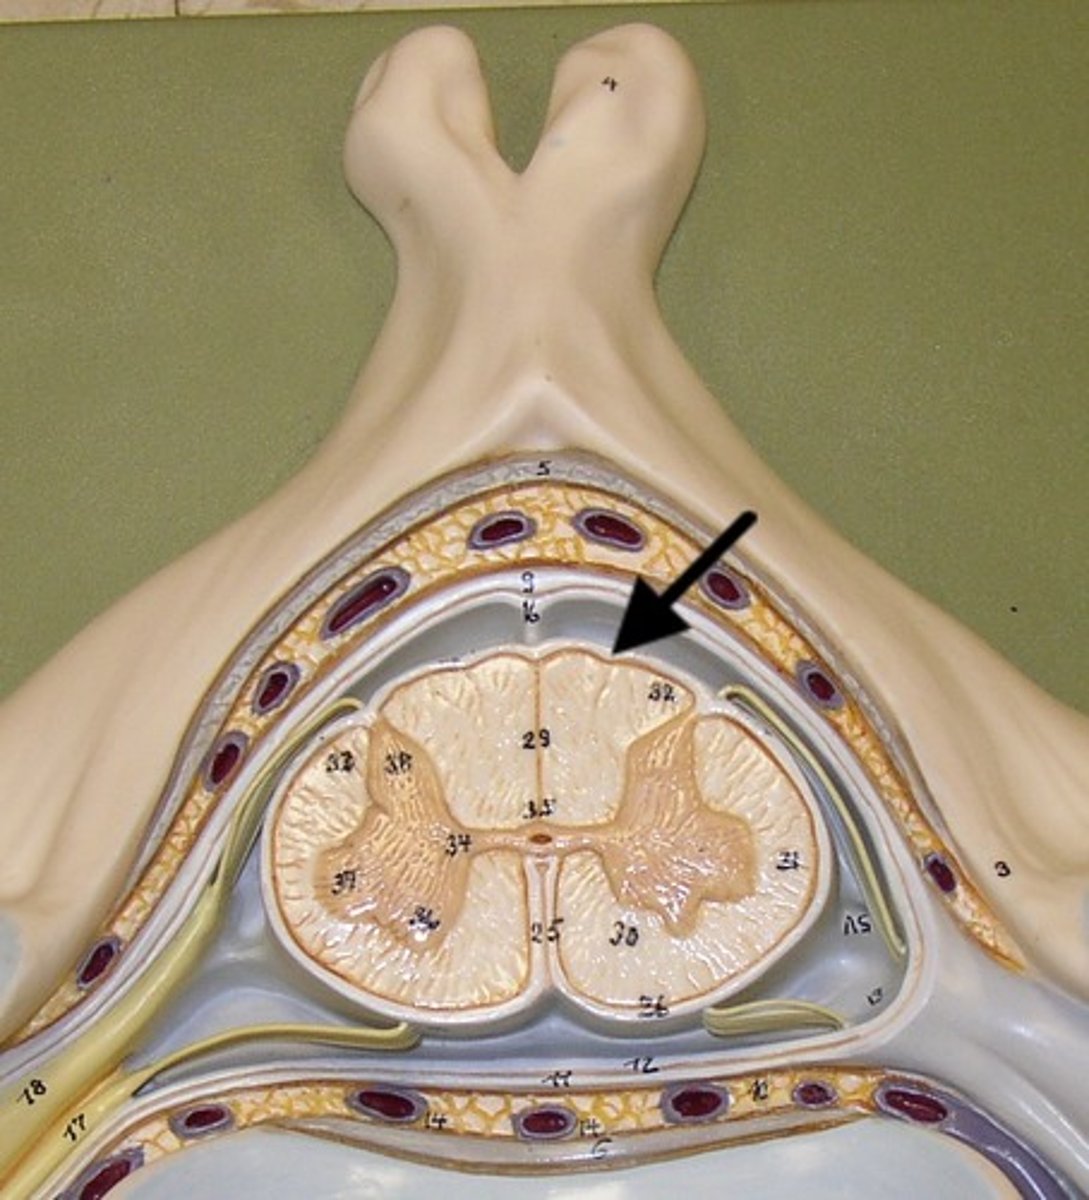

meninges

three protective membranes that surround the brain and spinal cord (AKA: the "maters")

pia mater

thin, delicate inner membrane of the meninges

arachnoid mater

middle layer

dura mater

Outermost layer of the meninges

denticulate ligament

subarachnoid space

contains cerebrospinal fluid

lateral corticospinal tract

dorsal root ganglion

ventral root